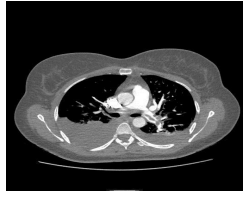

Mulher, 58 anos, hipertensa, em uso de losartan 100 mg e atenolol 100 mg, apresenta relato

de dispneia progressiva aos esforços, dorsalgia à esquerda,

perda peso e calafrios vespertinos. Na consulta de retorno,

traz exame solicitado (CT tórax), conforme imagem ao lado.

De acordo com esse achado, foi realizada uma toracocentese. A análise do líquido mostrou uma relação proteína pleural/sérica > 0,5 e DHL pleural/sérica > 0,6 com dosagem de ADA de 80 ui/L (VR: até 40 ui/L). Considerando essas informações, o diagnóstico é